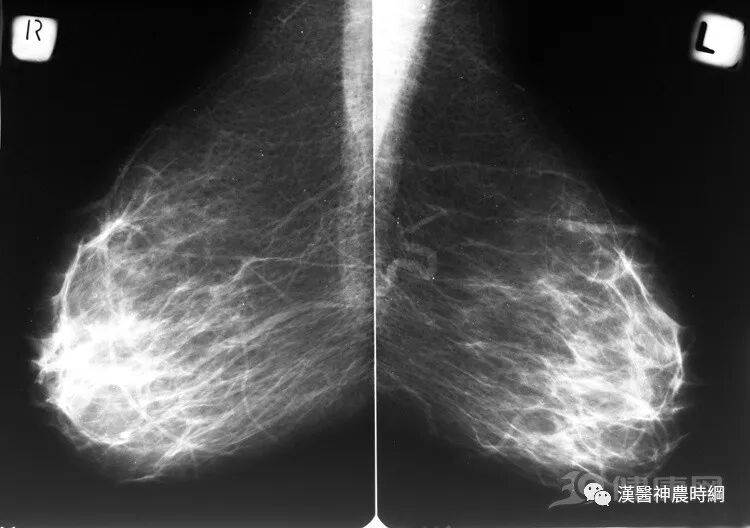

這樣情況下的女性可能易患乳腺癌?

乳腺癌

女性的頭號殺手

哪些女性容易患乳腺癌

乳房赋予了女人特有的美丽及性感,也使女性易患上乳腺癌。但是到底哪些女人容易罹患乳腺癌呢?